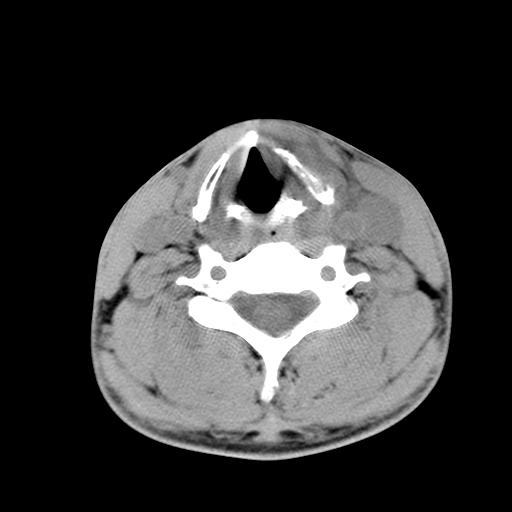

标题: CT15118:f-27y,左颈部肿一个月,无发热、无压痛 [打印本页]

标题: CT15118:f-27y,左颈部肿一个月,无发热、无压痛

1、甲状腺左叶病变:腺瘤?结节性增生?其他?

2、上极周围间隙病变。

3、2者关系?

左侧甲状腺肿大,密度不均.同侧甲状软骨似有破坏(建议传骨窗).左侧颈静脉增粗,各组织之间分界不清,有多个肿大淋巴结.甲状腺肿并感染?临床症状不符.淋巴结核?请结合其他检查.